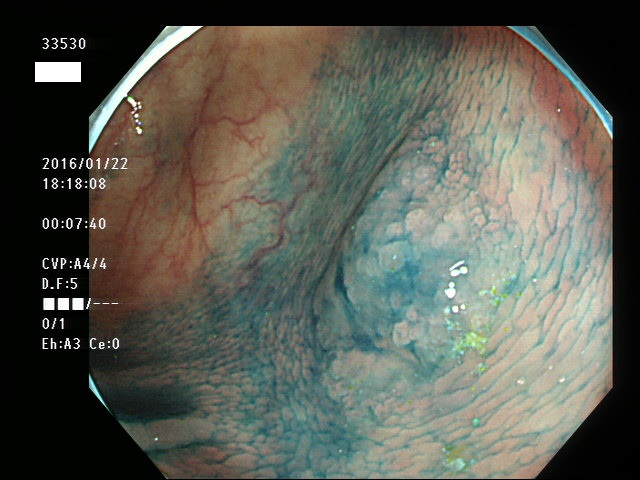

上記100名より抽出した平坦・陥凹型腺腫(=癌化の危険が高いが見落としやすい病変)の内視鏡写真

33500 33501 33505 33507 33508 33509 33510(SSA/Pのみ) 33511 33512 33514 33517 33519 33523 33528 33529 33530 33535 33537 33538 33539 33540 33544 33546 33547 33548 33549 33550 33552 33553 33555 33558 33559 33562 33563 33567 33571 33576 33578 33580 33581 33583 33585 33586 33587 33589 33590 33594 33595 33596 33599 ・・・・・・の50名